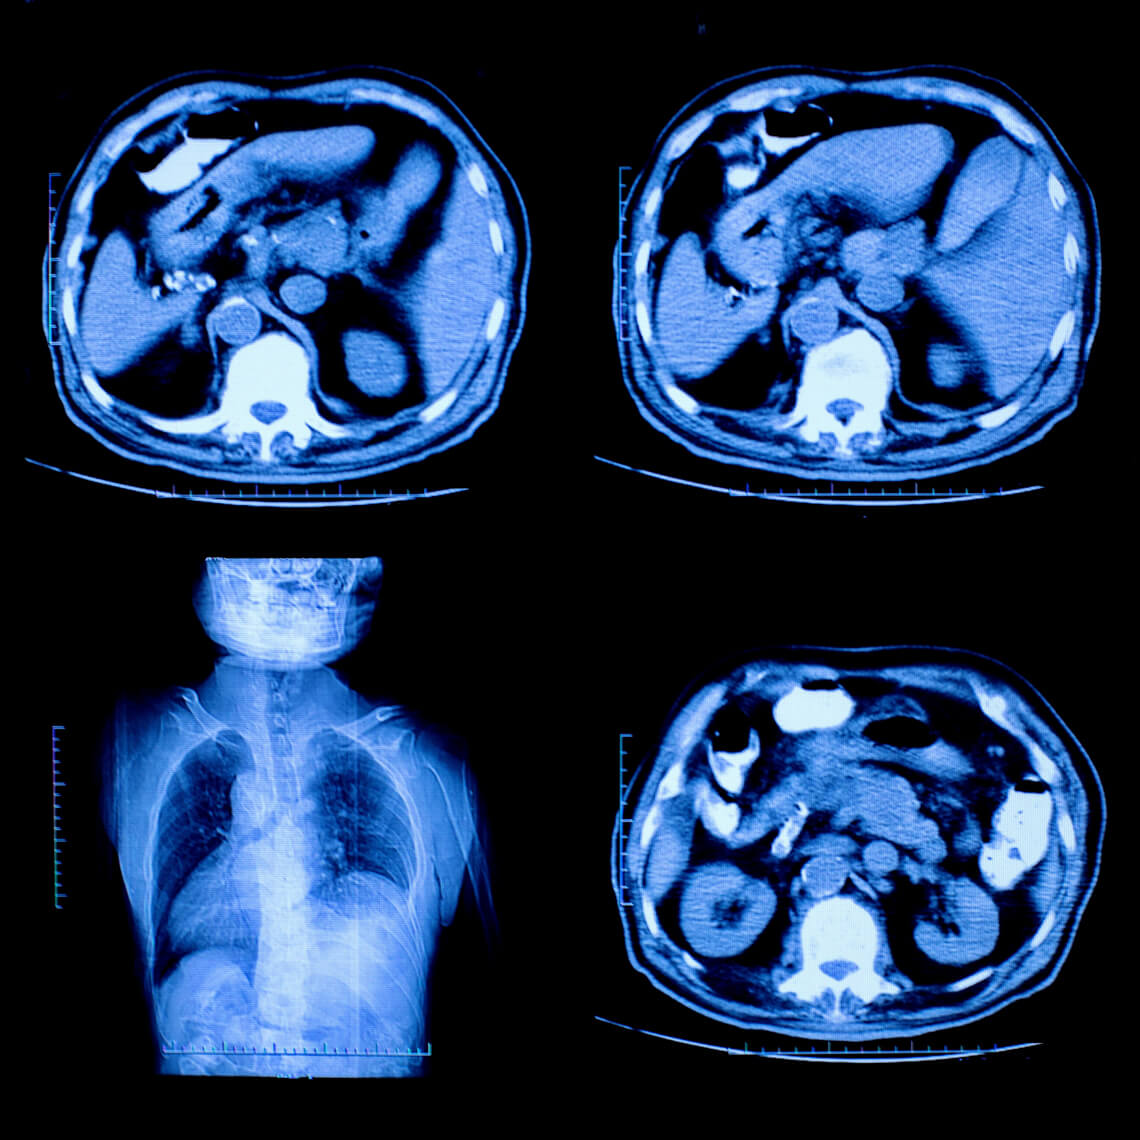

Contributing Factors in MedMal Cases Against Radiologists: How to Protect Your Patients and Yourself Deep analysis of more than a decade of medical professional liability cases reveals the most common factors which underlie cases involving radiologists. What’s my risk?

Interventional Radiology Guidelines The AMC PSO has published a set of guidelines in an effort to combat emerging risks in the delivery of interventional radiology. This collection of materials is meant to help standardize practice around a wide variety of topics within the field. How can we make radiology safer? |